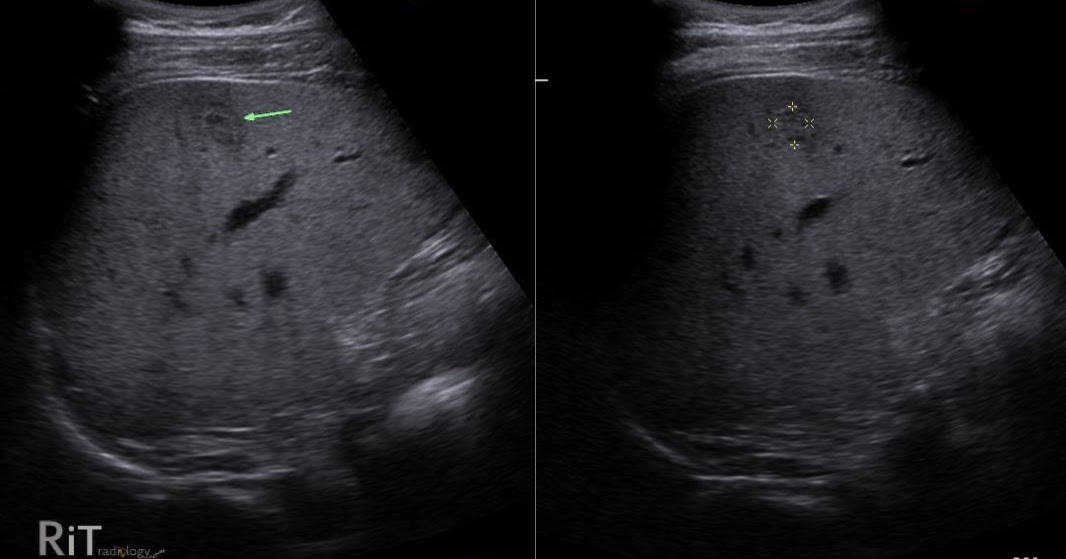

RiT radiology Atypical Hepatic Hemangioma Echoic Border Source: radiologyinthai.blogspot.com